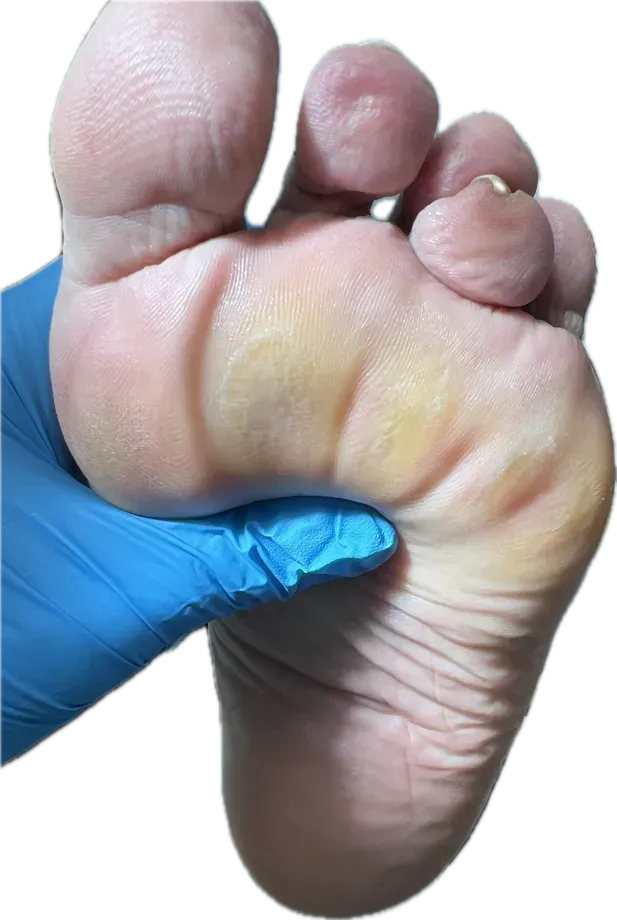

Exploración Podológica: Hiperqueratosis y Alteración del Apoyo

En la exploración clínica, tanto en descarga como en carga, observamos varios hallazgos significativos:

Signos clínicos encontrados

- Prominencia palpable de las cabezas metatarsianas, especialmente en los metatarsianos menores (del 2º al 5º)

- Hiperqueratosis marcada en antepié: zonas de dureza o callosidad que indican sobrepresión mantenida

Metatarsalgia bilateral por sobrecarga mecánica, en paciente con diabetes mellitus, asociada a alteración biomecánica del apoyo (pie equinizado), atrofia del panículo adiposo plantar e hiperpresión mantenida en metatarsianos menores.